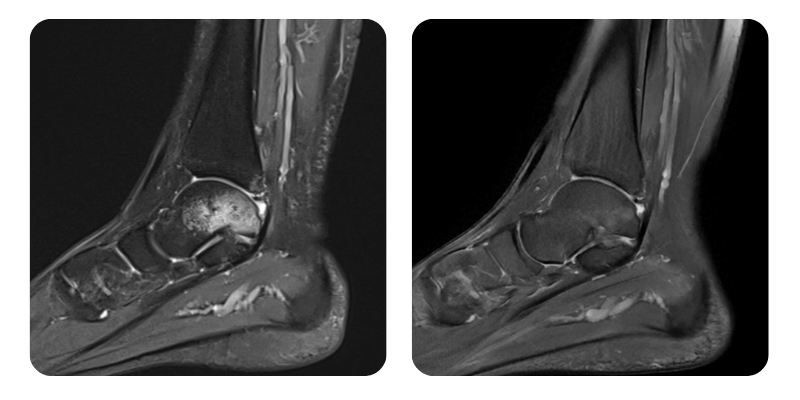

Before

After

B.A.A., 25 years old - Post-contusion bone edema of the left talus.

Diagnosis: Post-contusion bone edema of the left talus, left calcaneus, left cuboid, and at the level of the left medial and lateral malleoli; rupture of the left anterior talofibular ligament; edema of the posterior talofibular ligament and the deep portion of the deltoid ligament; joint effusion.

Evolution: An approximate 90% reduction in edema was observed.